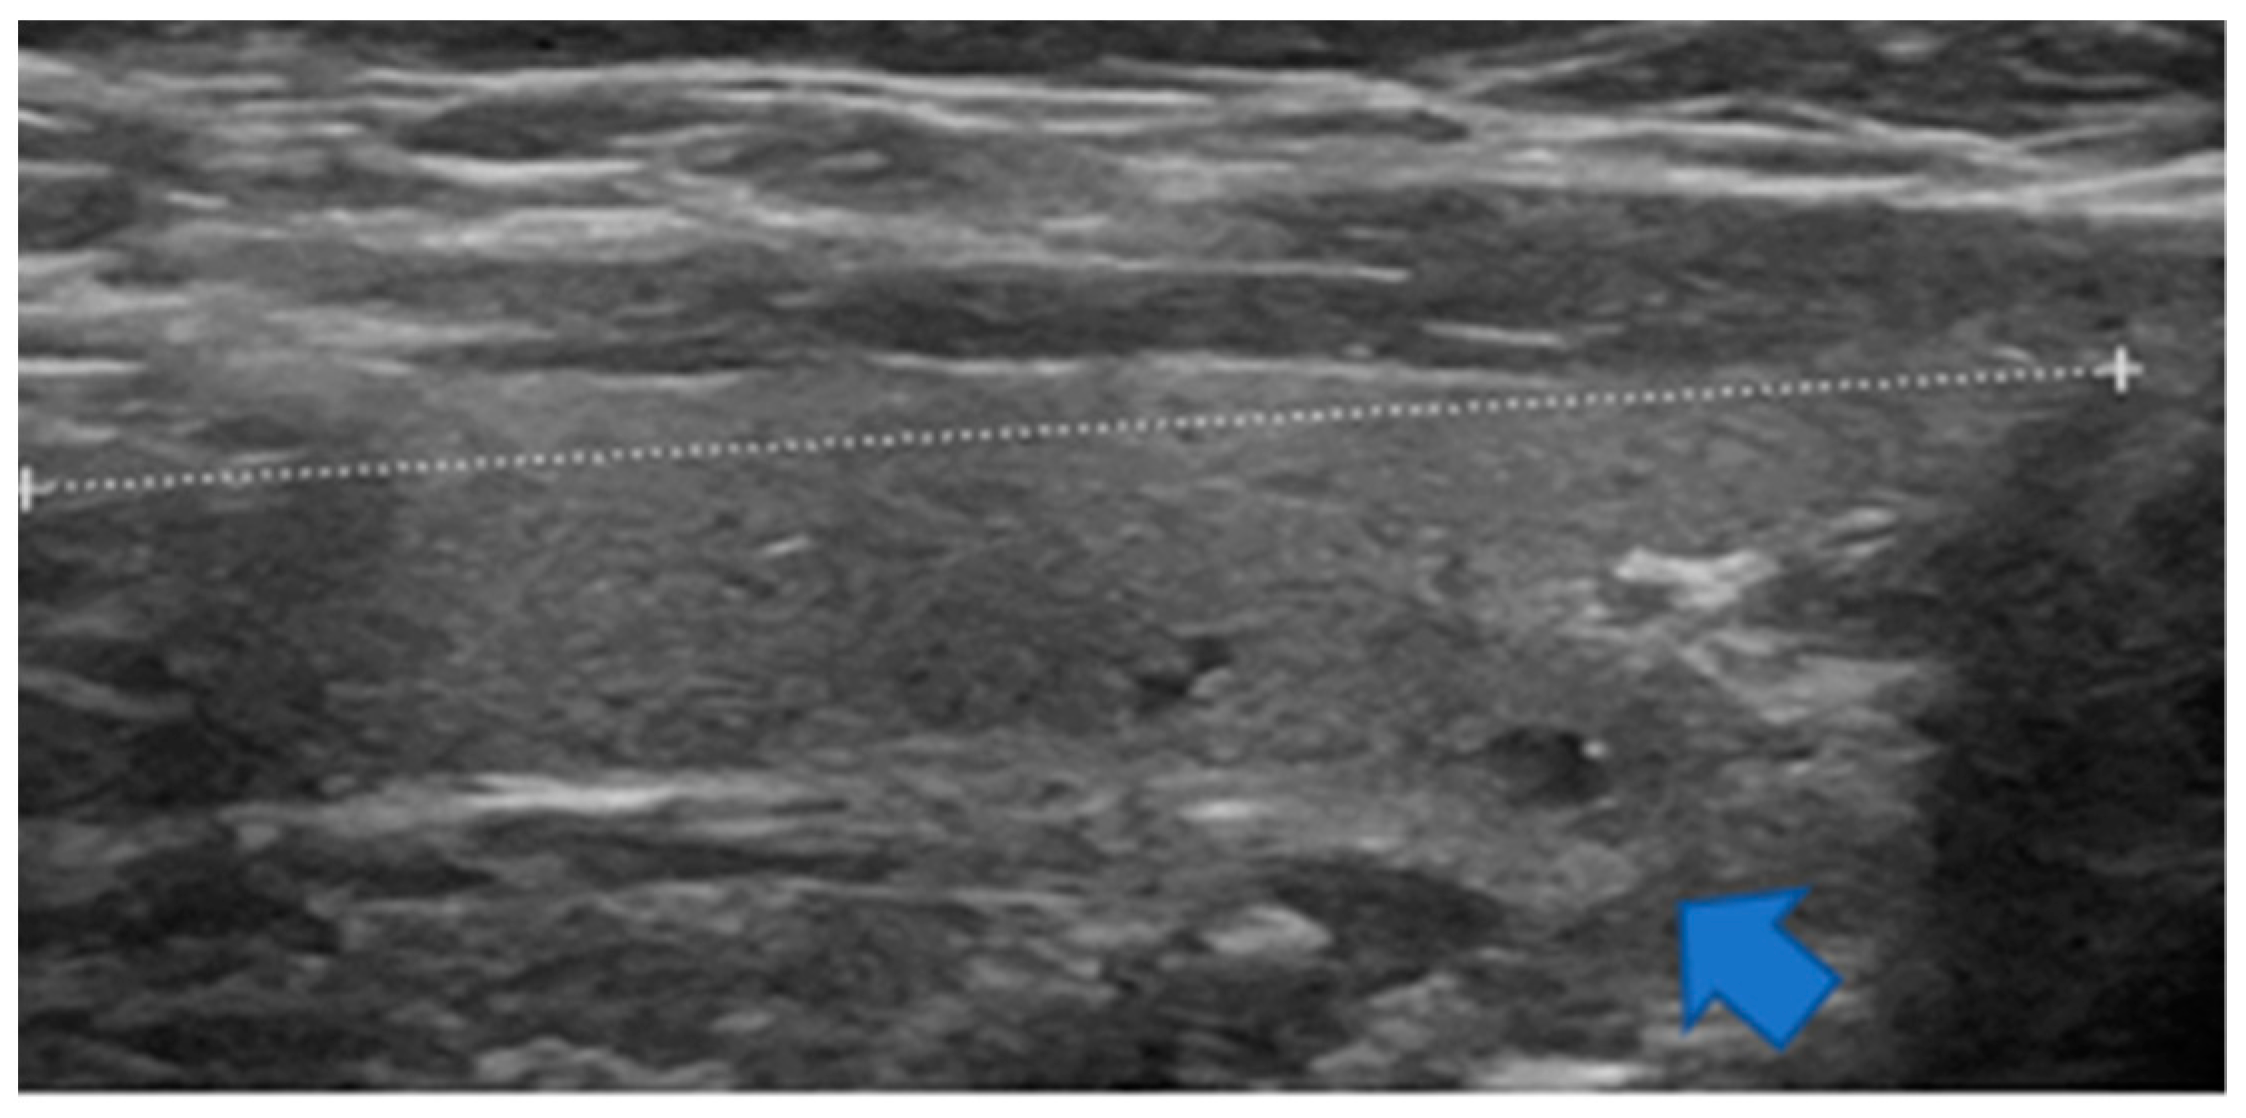

Figure 3.

Sagittal view of a non-enlarged thyroid lobe. At the lower portion, there is a downward and backward protrusion named the posteroinferior horn herein (blue arrow).